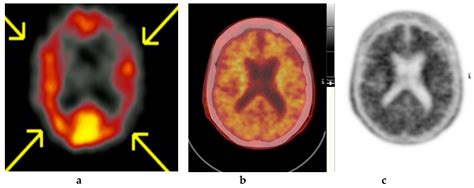

Combination Imaging

Combining Amyloid PET Imaging with other imaging modalities, such as magnetic resonance imaging (MRI) or functional PET, can provide a more comprehensive assessment of brain structure and function. This multi-modal approach could improve diagnostic accuracy and treatment planning.